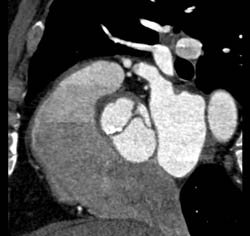

Aortic Stenosis With Dilated Aortic Root